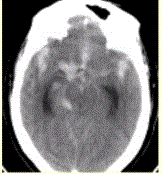

问题 患者男,50岁,突发昏迷、呕吐1h。查体:颈项强直,脑膜刺激征阳性,CT表现如图1。 有关动脉瘤,描述正确的是

选项 A.根据形态分为囊状、梭形、夹层及假性层动脉瘤 B.囊状15%发生于颅底willis环或椎基底动脉尖 C.梭形动脉瘤好发于颅底willis环 D.无血栓动脉瘤由于存在流空效应,在T1WI和T2WI上均为高信号 E.动脉瘤脑血管造影均为阳性

答案 A